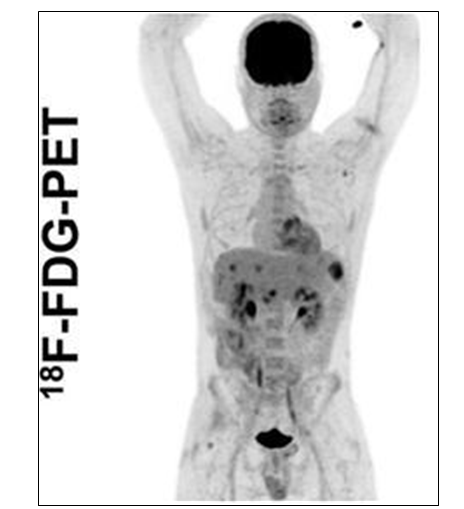

양전자 방출 단층촬영(positron emission tomography, PET)은 양전자를 방출하는 방사선 의약품을 체내에 투여한 후 PET 촬영기를 이용하여 그 물질의 분포를 영상화(그림)하는 기법이다. 가장 많이 사용되는 18F-FDG(18F-fluorodeoxyglucose) PET는 포도당 대사를 영상으로 나타내며 전신영상을 얻을 수 있어 종양의 진단과 치료 평가에 사용된다. PET에서 활용하는 종양세포의 당 대사의 특징으로 가장 바른 설명은?

• 18F-FDG는 포도당 유사체로, 세포 내로 들어가 해당과정(glycolysis)의 초기 단계에서 대사된다. 하지만 해당 과정을 완전히 진행하지 못하고 포획되어 축적되면 PET 영상에서 확인이 된다.

• 정상 세포는 산소가 충분한 상황에서는 포도당을 이용해 TCA cycle을 돌려 36 ATP를 생산하고, 무산소 상황에서만 anaerobic glycolysis를 진행한다. 반면 종양세포는 산소의 유무에 상관없이 해당과정이 활성화되며, 이를 Warburg effect라 한다.